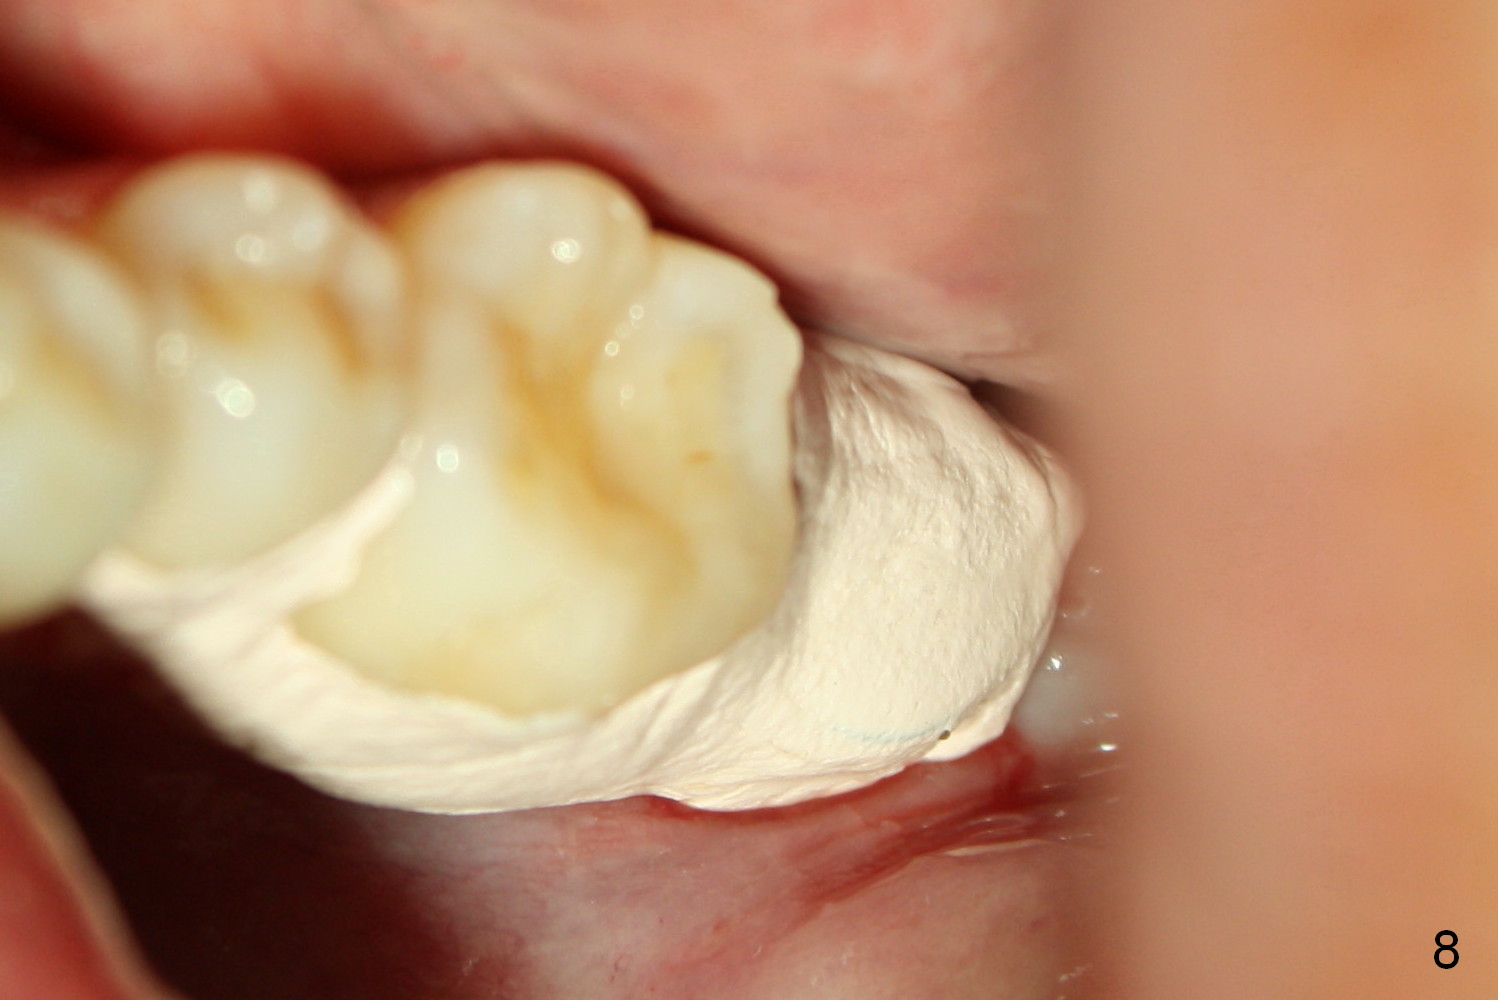

A 48-year-old lady is a dental phobic, requesting extraction of the lower left 2nd molar (Fig.1).   She returns for implant placement 9 months post extraction (Fig.2).  The ridge is mildly to moderately atrophic.  It appears that a 5x12 mm implant is appropriate for the site (Fig.3).  For safety, osteotomy is initiated at the depth of 10 mm; it appears that there is enough height for a 12 mm implant (Fig.4).  The depth is controlled by drill stopper (Fig.5 S).  Finally a 5x12 mm implant is apparently safely placed (Fig.6).  A healing abutment is placed and the incision is sutured with 4-0 Chromic gut (Fig.7).  Perio dressing is applied around the healing abutment for wound protection (Fig.8).  It appears that the healing abutment (Fig.8': *) helps stabilize the perio dressing, which remains in place 1 week postop.  When the perio dressing is removed, the wound around the healing abutment is healing (Fig.9).  There is no bone loss around the implant 3 months postop (Fig.10 (H: healing abutment), or 16 months postop (i.e., 9 months post cementation, Fig.11,12).  The patient complains of pain when she chews with the implant crown, but pain stops whenever she does not bite.  Percussion does not elicit any discomfort.  The gingiva is healthy.  There is possibility of the buccal plate being thin or the lingual plate being perforated in the submandibular fossa.  If the discomfort remains the same next 6 months, CBCT will be prescribed.